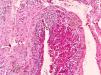

Bajo anestesia local, se realizó la extirpación completa de la lesión. Su evolución postoperatoria fue satisfactoria con remisión de la sintomatología y cicatrización de la herida quirúrgica. El estudio de histopatología reportó tumor de Masson, con hiperplasia endotelial papilar intravascular (figs. 2 y 3).